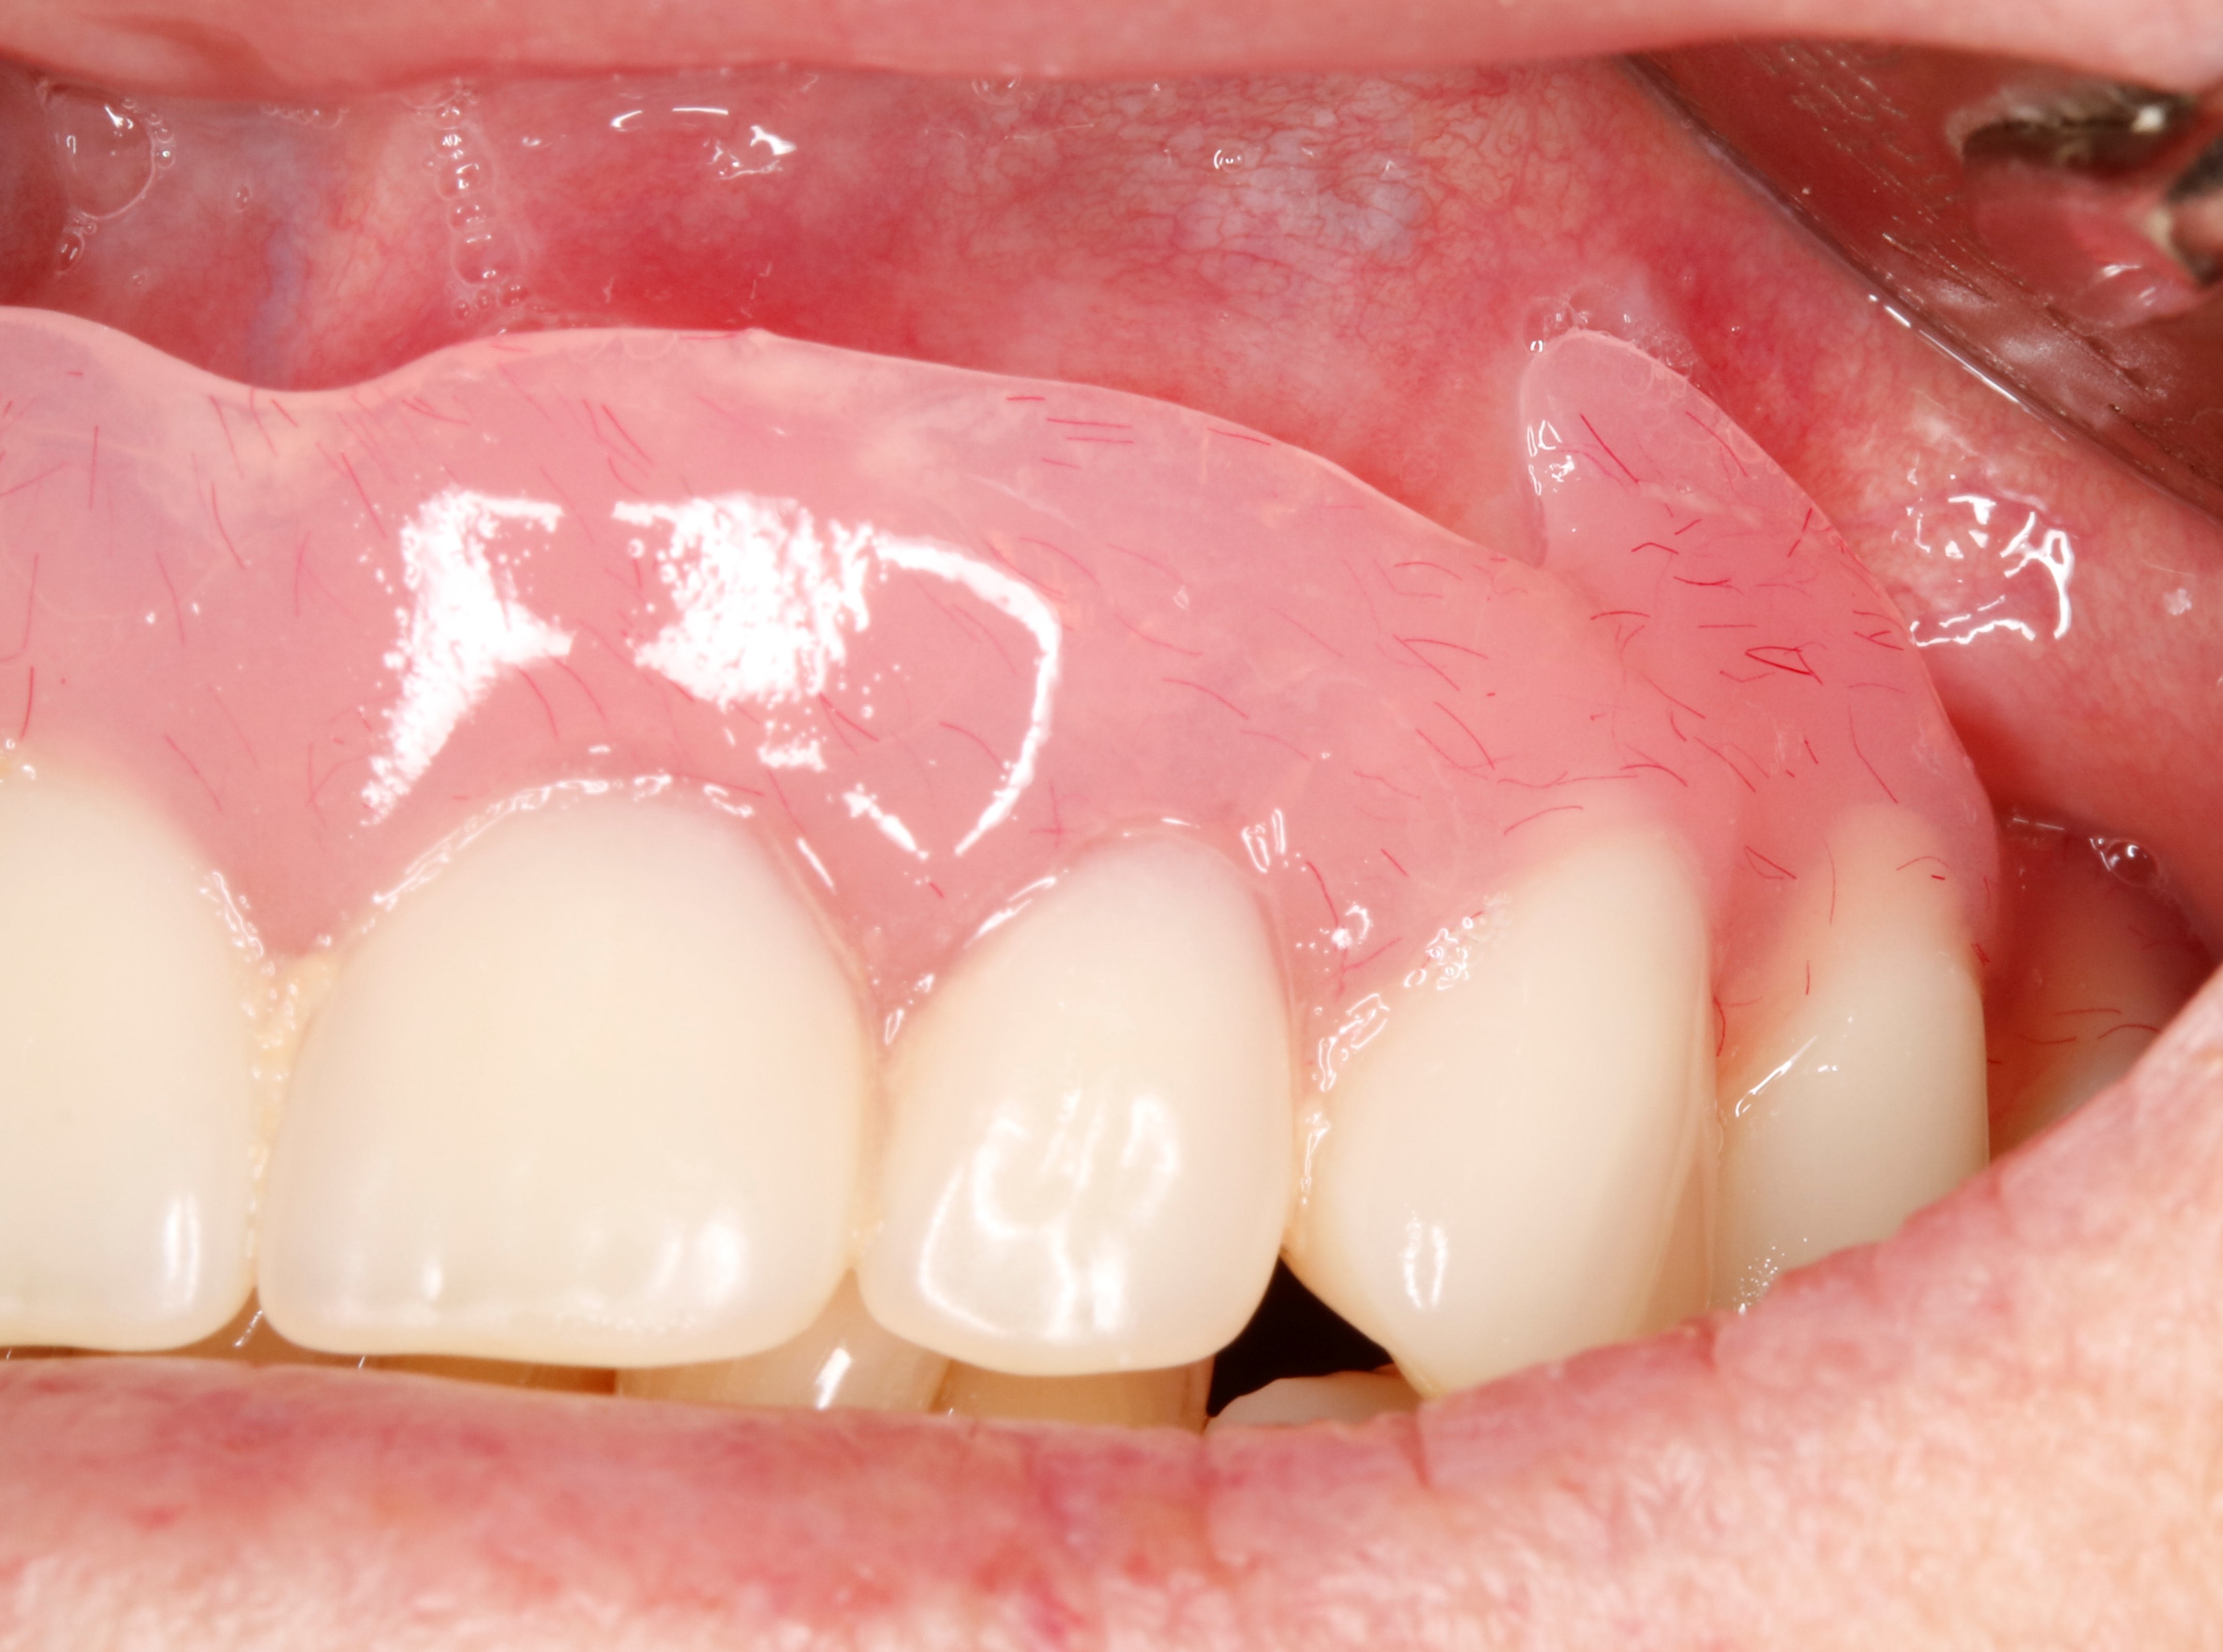

En fait c est un complet immediat suite a des extractions du bloc ant .

Et tu sais comme ils sont ces sto , ils te laissent des bosses de partout .

Du coup tout l os de devant est en contre depouille . D ou les crochets a os .

Enlaye tu trouves pas qu’en antérieur les bords sont fins ? Et que ça risque de blesser ? Ou alors il y a une subtilité qui m’échappe encore ??

Junior , bien obligé de faire fin devant sinon ça lui ferait une bouche de babouin .

non ,je ne met rien ,pas de fit ou de quoique ce soit . dans 3 semaines environ , je ferais un rebasage .

et si l'os me le permet je monterais devant .en attendant ,il faut gratter par ci par là .